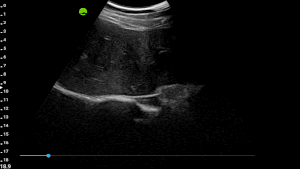

Dynamic, multi-planar probe positioning assistance overlaid directly on the ultrasound image

Built from a dataset of millions de-identified ultrasound images, our AI models cover Obstetrics, Cardiology, and Gynecology. They analyze key anatomical structures in real time, providing accurate biometric measurements and insights that help clinicians assess fetal growth, cardiac function, and organ health with greater speed and confidence.